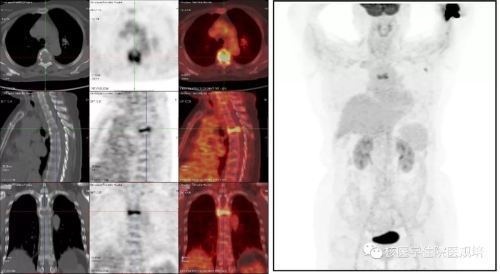

病史及检查目的: 患者63岁女性,4月余前无明显诱因出现持续性胸背部疼痛,沿肋间放射至胸部,左侧重,翻身及行走后加重,查体T4棘突压痛及叩痛(+)。行胸椎CT平扫+三维重建提示T4椎体变扁,后缘可见软组织密度影突向髓腔内,硬膜囊受压,考虑T4椎体病理性骨折可能。实验室检查:尿本周蛋白阴性;尿KAPPA轻链及LAMBDA轻链阴性;肿瘤标志物检测均为阴性。 为明确T4椎体病变性质、寻找骨转移原发灶行PET/CT检查(图2)。 图1.胸椎CT(骨窗) 图2. PET/CT图像 检查所见: T4椎体及附件区域见条状高度放射性浓聚(SUVmax:8.1),CT于相应区域可见溶骨性骨质破坏及软组织肿物影,向后累及附件并突入椎管内,椎体前缘骨皮质尚完整。左腋窝可见一FDG摄取增高淋巴结显影,考虑淋巴组织回流所致。扫描范围其余部位未见明显异常。 检查意见: T4椎体及附件骨质破坏呈葡萄糖代谢明显增高考虑恶性肿瘤可能,需鉴别原发灶不明的转移瘤、浆细胞瘤、骨巨细胞瘤、骨的嗜酸性肉芽肿及不典型淋巴瘤等,建议组织病理学检查。 手术及病理: 行胸椎椎管减压、椎弓根钉内固定术、病灶清除、椎体成形术,积水潭医院病理会诊:(胸4椎体)富含多核巨细胞病变,组织形态首先考虑骨巨细胞瘤。免疫组化:CK(-),Desmin(-),Ki67(10%-15%+),Vimentin(+),ActinSM(-),PGM-1(多核巨细胞+),KP-1(多核巨细胞+)。 病例相关知识: 骨巨细胞瘤(giant cell tumor of bone,GCT)为一种临床较为常见的骨原发性肿瘤,大部分为良性肿瘤,部分生长活跃,极少数一开始就是恶性。GCT具有丰富的血管组织并含有单核基质细胞和很多破骨细胞样的多核巨细胞,其中基质细胞决定肿瘤的性质。Jaffe等[1]首次定义GCT并根据基质细胞的异型性及有丝分裂活动进行病理分级,一般认为I级偏良性,Ⅲ级为恶性,介于两者之间的为Ⅱ级。目前WHO第四版骨与软组织肿瘤已将GCT定义为交界性肿瘤。与西方国家相比,国内GCT的发病率较高,约占所有原发骨肿瘤的20%[2]。女性发病率高于男性,多发生于青壮年,发病年龄多在20-40 岁之间,50岁以上的GCT约占9%-13%,青年人和儿童少见[3]。GCT多发生于骨骺融合后成熟的骨端[4],侵犯长骨多见,*常见于股骨下端、胫骨上端,约占50%以上,发生于非长管状骨如脊柱、骨盆、手骨、颌骨、颅骨等的GCT约占20%,但近年来也有报道GCT在脊柱的发病率增加。该病*常见的症状为肿瘤部位的疼痛与肿胀,且疼痛有活动后加重、休息后缓解的特点,手术是治疗GCT的主要方法,目前亦有一些RankL拮抗剂用于术前药物治疗。 GCT的影像表现具有一定特异性,X线平片表现为骨端偏心性、囊性、膨胀性、溶骨性骨质破坏, 无明显硬化缘,骨包壳完整或部分缺如,部分肿瘤内可见骨性分隔,呈“皂泡样”改变(图3)。CT较X线具有较高的分辨率,能更加细致入微地观察骨质破坏情况,可观察到骨质破坏区内残留的骨嵴,与X线平片上“皂泡样”改变相对应,还可以能清晰地显示破坏区内部结构及软组织肿块及周边残留的骨壳。MRI检查能够清晰显示骨巨细胞瘤的大小、位置及形态,且对肿瘤附近的水肿状况进行清晰显示,在诊断病变范围上的价值较X线与CT检查更高。在MRI检查中,肿瘤的实质部分多呈T1WI与T2WI等信号,其内常可见多发混杂信号影,提示肿瘤内部常伴有坏死、囊变和出血。 图3. 骨巨细胞瘤的皂泡样改变(左:X线片,右:99mTc-MDP骨显像)(北京大学人民医院提供) 尽管骨肿瘤的*终诊断的确立需要临床、影像、病理三结合,即“CRP诊断”,但典型的影像表现对早期临床诊疗决策的建立十分重要。18F-FDG PET/CT全身大视野成像有助于发现肿瘤累及区域,通过发现多发病灶,首先可帮助检出转移瘤或血液系统肿瘤。然而,本病例PET/CT所见为脊柱单发病变,其鉴别诊断面临更多的挑战。由于病灶呈溶骨性骨质破坏并软组织肿物形成,椎体出现病理性骨折且软组织肿物压迫硬膜囊,同时肿瘤呈FDG高摄取,鉴于患者年龄偏大,应首先怀疑恶性病变。患者无肿瘤标志物升高且PET/CT无原发肿瘤病灶显示,不支持上皮源性肿瘤脊柱转移,但从发病机率应考虑有无原发灶隐匿的可能性;病变椎体前缘保留较完整,提示肿瘤侵袭性不强,不符合侵袭性淋巴瘤或一些高度恶性肉瘤的常见表现;单发浆细胞瘤多为溶骨性且可呈膨胀性改变,破坏区可见残留的骨壳和骨嵴,但一般FDG摄取程度相对较低;骨的嗜酸性肉芽肿属于朗格汉斯组织细胞增生症虽可累及脊柱并出现病理性骨折,其FDG摄取程度亦较高,但该病多见于年轻人群。回顾性分析该患者年龄虽然不属GCT好发人群,但亦可发病,而较高的FDG摄取和较温和的骨质破坏可符合GCT表现,然而由于椎体压缩性骨折使得CT对肿瘤形态和内部结构改变的观察不满意。若能获得典型的GCT CT表现,GCT诊断应该首先考虑(图4)。 图4.典型脊柱骨巨细胞瘤的PET/CT及MRI(北京大学人民医院提供) 对于原发性骨肿瘤,18F-FDG PET/CT的摄取与肿瘤成分密切相关,富含巨细胞的肿瘤(骨巨细胞瘤、未分化肉瘤、朗格汉斯组织细胞增生症等)多可见较高FDG摄取,甚至高于常见的恶性骨原发性肿瘤(骨肉瘤、软骨肉瘤、尤文肉瘤等),而良性肿瘤或者细胞成分稀疏的恶性肿瘤FDG摄取程度较低。 小结: 本病例并非典型的骨巨细胞瘤,通过此病例提出这一临床可能遇到的情况,希望为规培的小伙伴们提供脊柱病变的鉴别诊断思路。同时强调对于骨肿瘤的诊断一定是临床、影像、病理的综合分析,对常见的骨原发肿瘤相关知识应加以了解。 作者:中日友好医院核医学科 韩萍萍 郑玉民 参考文献: [1] Jaffe Hk, Lichtenstein L, Portis RB. Giant cell tumor of bone: Its pathologic appearance, grading, supposed variants and treatment. Arch Pathol, 1940, 30: 993. [2] Szendröi M. Giant-cell tumour of bone. J Bone Joint Surg Br, 2004, 86: 5-12. [3]Murphey MD, Nomikos GC, Flemming DJ, et al. From the archives of AFIP. Imaging of giant cell tumor and giant cell reparative granuloma of bone: radiologic-pathologic correlation. Radiographics, 2001, 21: 1283-1309. [4] 段承祥,王晨光,李健丁主编. 骨肿瘤影像学. 科学出版社, 2004年第一版。